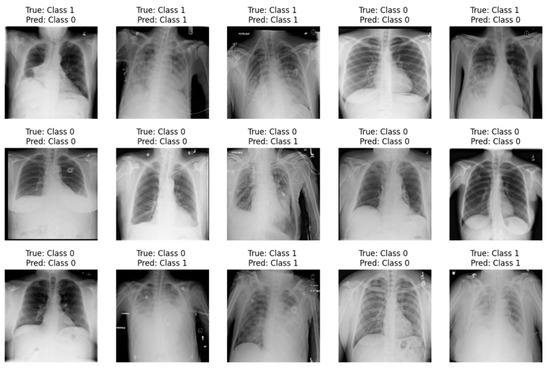

3.8. Qualitative Evaluation of CNN and ResNet50 Models